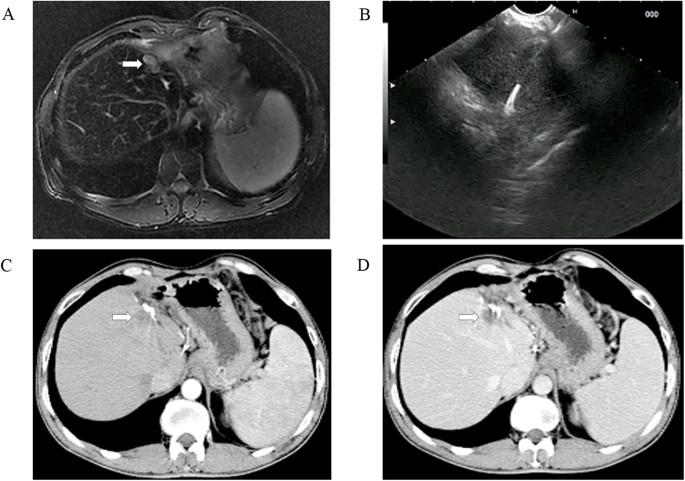

EUS-guided anhydrous ethanol ablation for postoperative liver recurrence of hepatocellular carcinoma.

(A) presence of a 1.5 cm × 1.1 cm postoperative liver recurrence located on the resection margin as shown on T2-weighted MRI scans (white arrows), but conventional US image failed to show the lesions; (B) EUS-guided ethanol injection; and (C) arterial phase (arrowhead) and (D) parenchymal phase (arrowhead): non-enhanced liver disease on follow-up contrast CT scan revealed complete resolution of disease at 12 months.

All patients were followed up for 1–2.5 years as scheduled. At 12 months after treatment, 12 of 13 (92.3%) patients achieved complete tumor response in iodine-125 particle implantation (Fig. 1) while 3 of 10 (30%) in anhydrous ethanol ablation (Fig. 3 and Table 4). Residual tumor was detected in 8 patients after anhydrous ethanol ablation (n = 2) or iodine-125 particle implantation (n = 6); these patients were further treated with second-look EUS-guided interventional treatment (n = 5) and radiotherapy (n = 2) and surgical resection (n = 1). Complete response was achieved after again EUS-guided treatment in 3 of 5 patients, whereas the remaining 2 patients required surgical resection but only one succeed. Recurrence was observed in 2 patients at 1 year after anhydrous ethanol ablation. No clinically significant late-onset complications occurred.